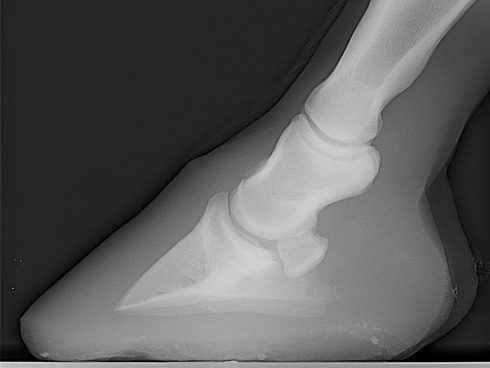

what is this condition

laminitis, rotation of P3

what is this

a normal hoof, note parallel angle